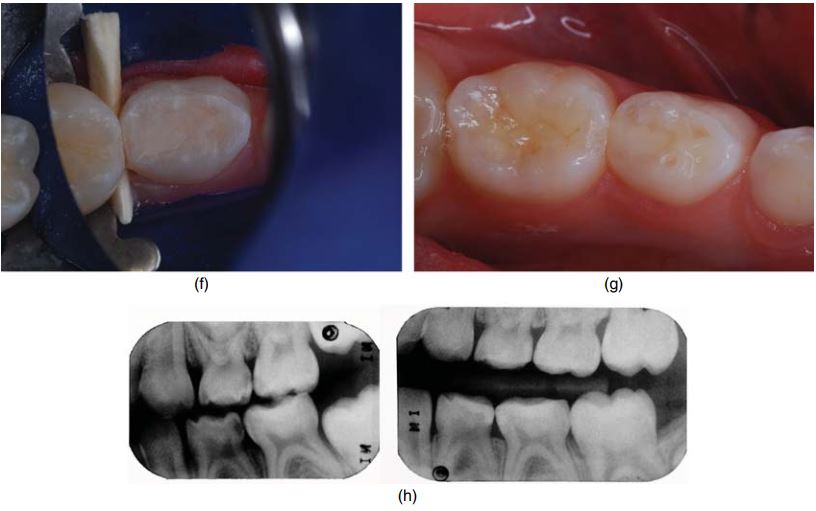

Hình 4.2a đến 4.4g minh họa trám răng cối sữa bằng RMGI.

Vật liệu glass ionomer phối hợp nhựa (RMGI) được khuyên chỉ định cho xoang I, II và V, vì nó có những ưu điểm của glass ionomer cổ điển. Việc phối hợp thêm nhựa giúp cải thiện nhiều đặc tính vật lí như kháng gãy, kháng mòn và tăng thẩm mĩ.

RMGI trùng hợp bằng đèn và bằng phản ứng hóa học giữa acid và base. Thế hệ vật liệu mới nhất hiện nay là “nano – ionomer” (Ketac Nano, 3M ESPE).

Trám răng bằng RMGI cũng cần cách li tốt, tuy nhiên nó ít gây nhạy cảm và thời gian làm việc ngắn hơn so với vật liệu composite. Đây là yêu cầu rất quan trọng khi điều trị răng trẻ em.

Vật liệu glass ionomer kết dính vào men và ngà bằng hóa học, có khả năng phóng thích fluoride ra mô răng lân cận, hệ số giãn nở nhiệt tương đương răng, tương hợp sinh học, ít nhạy cảm với độ ẩm hơn composite và compomer.

Tuy nhiên glass ionomer không có các đặc tính vật lí tốt, kháng mòn kém, do đó hạn chế sử dụng đơn độc khi trám xoang I hoặc V. Glass ionomer có thể được sử dụng trám lót bên dưới lớp composite, giúp kết dính tốt với răng và phóng thích fluoride.

Glass ionomer độ nhớt cao thường được lựa chọn để trám răng vì dễ sử dụng và có nhiều đặc tính vật lí tốt. Glass ionomer phóng thích fluoride tại chỗ, tính thẩm mỹ tương đối tốt, sử dụng được trong môi trường ẩm, dính vào răng bằng hóa học và trùng hợp bằng hóa học.

Trám GIC bằng con nhộng hoặc bằng súng giúp giảm đáng kể thời gian làm việc.

Sau khi đặt GIC vào xoang, sử dụng ngón tay ép xuống để loại bỏ phần dư (H1.8).